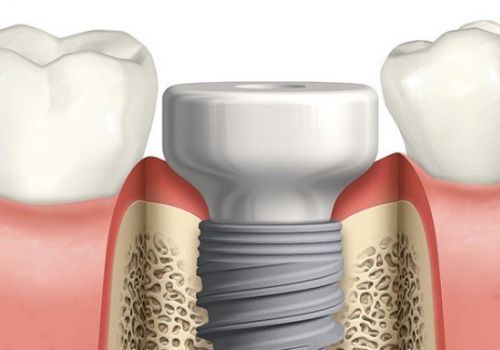

Trồng răng